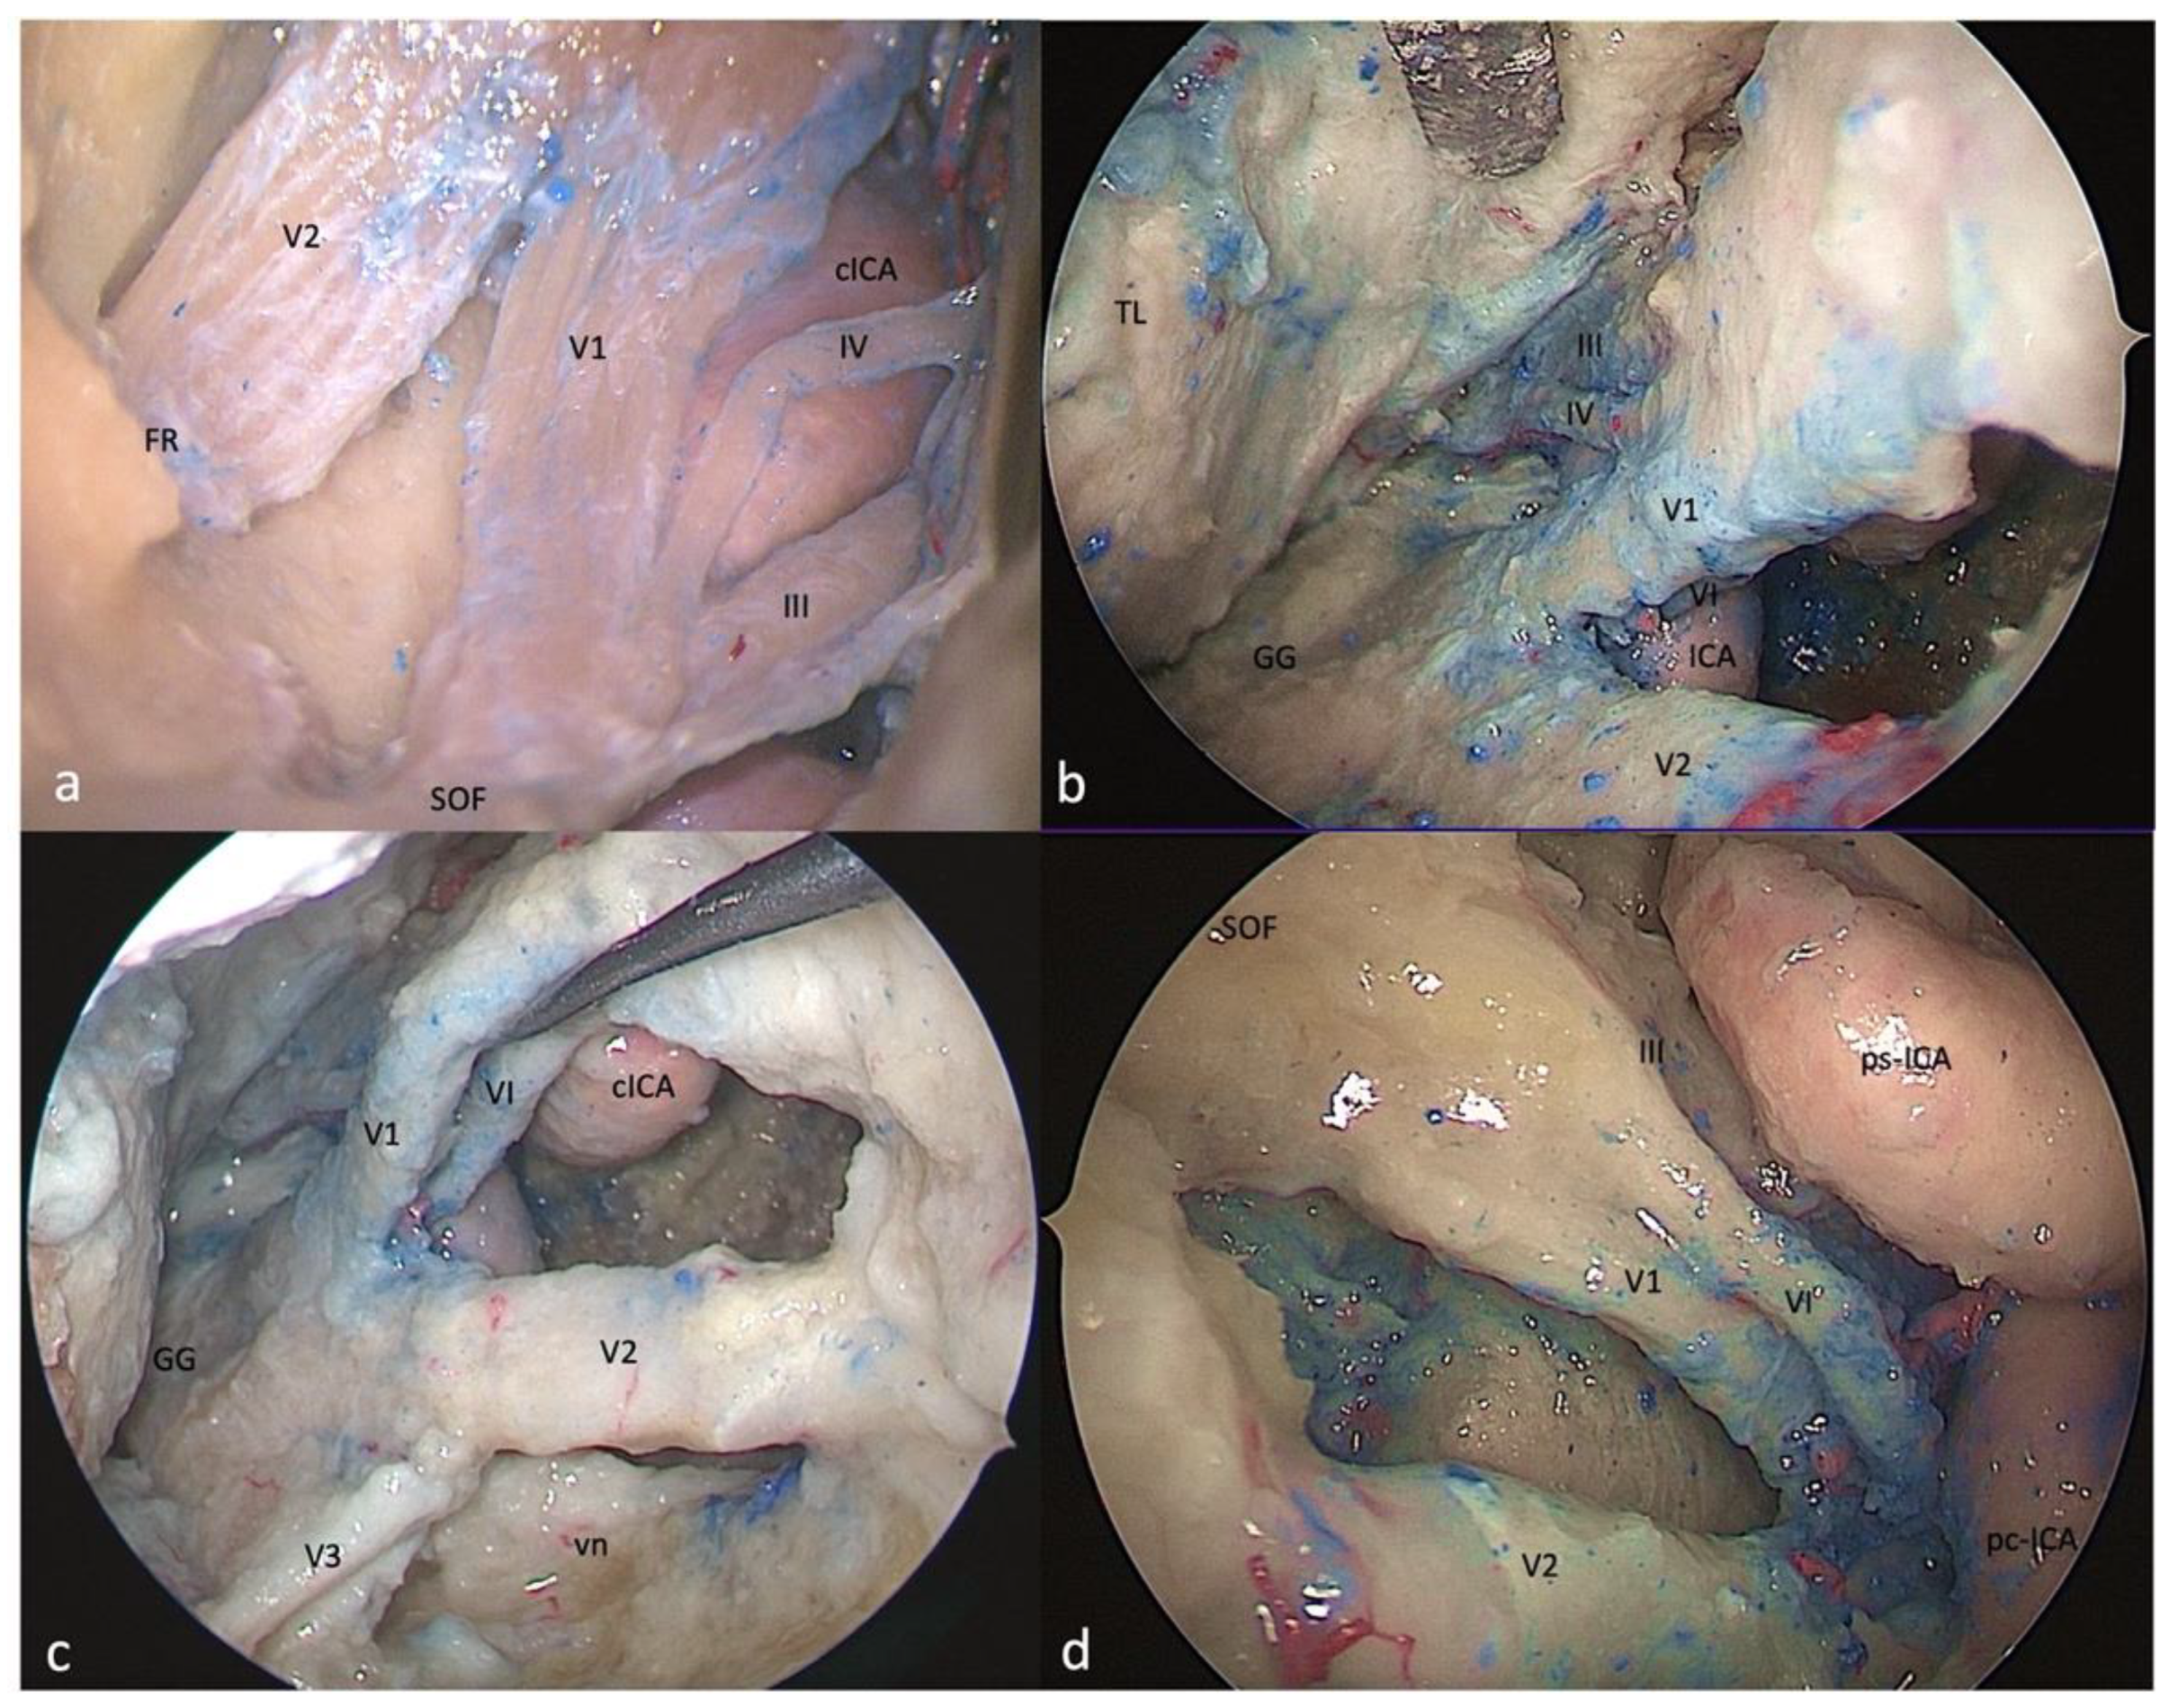

3.1. Clinoid Triangle (Dolenc’s Triangle)

3.1.1. FTOZ Perspective

3.1.2. SETOA Perspective

3.1.3. EEEA Perspective

3.2. Oculomotor Triangle (Hakuba’s Triangle)

3.2.1. FTOZ Perspective

3.2.2. SETOA Perspective

3.2.3. EEEA Perspective

3.3. Supratrochlear Triangle (Paramedian)

3.3.1. FTOZ Perspective

3.3.2. SETOA Perspective

3.3.3. EEEA Perspective

3.4. Infratrochlear Triangle (Parkinson’s triangle)

3.4.1. FTOZ Perspective

3.4.2. SETOA Perspective

3.4.3. EEEA Perspective

3.5. Anteromedial Triangle (Mullan’s Triangle)

3.5.1. FTOZ Perspective

3.5.2. SETOA Perspective

3.5.3. EEEA Perspective